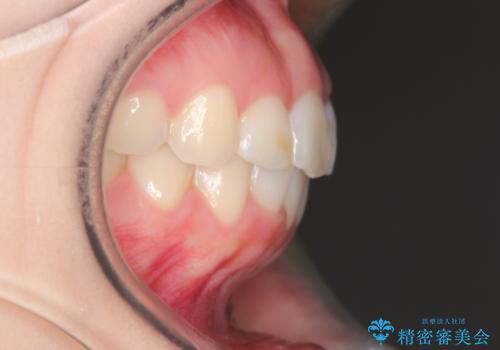

【インビザライン】前歯が出ているのを治したい

- 前歯が出ていることを主訴に来院されました。

前歯の突出感が改善され、満足していただきました。